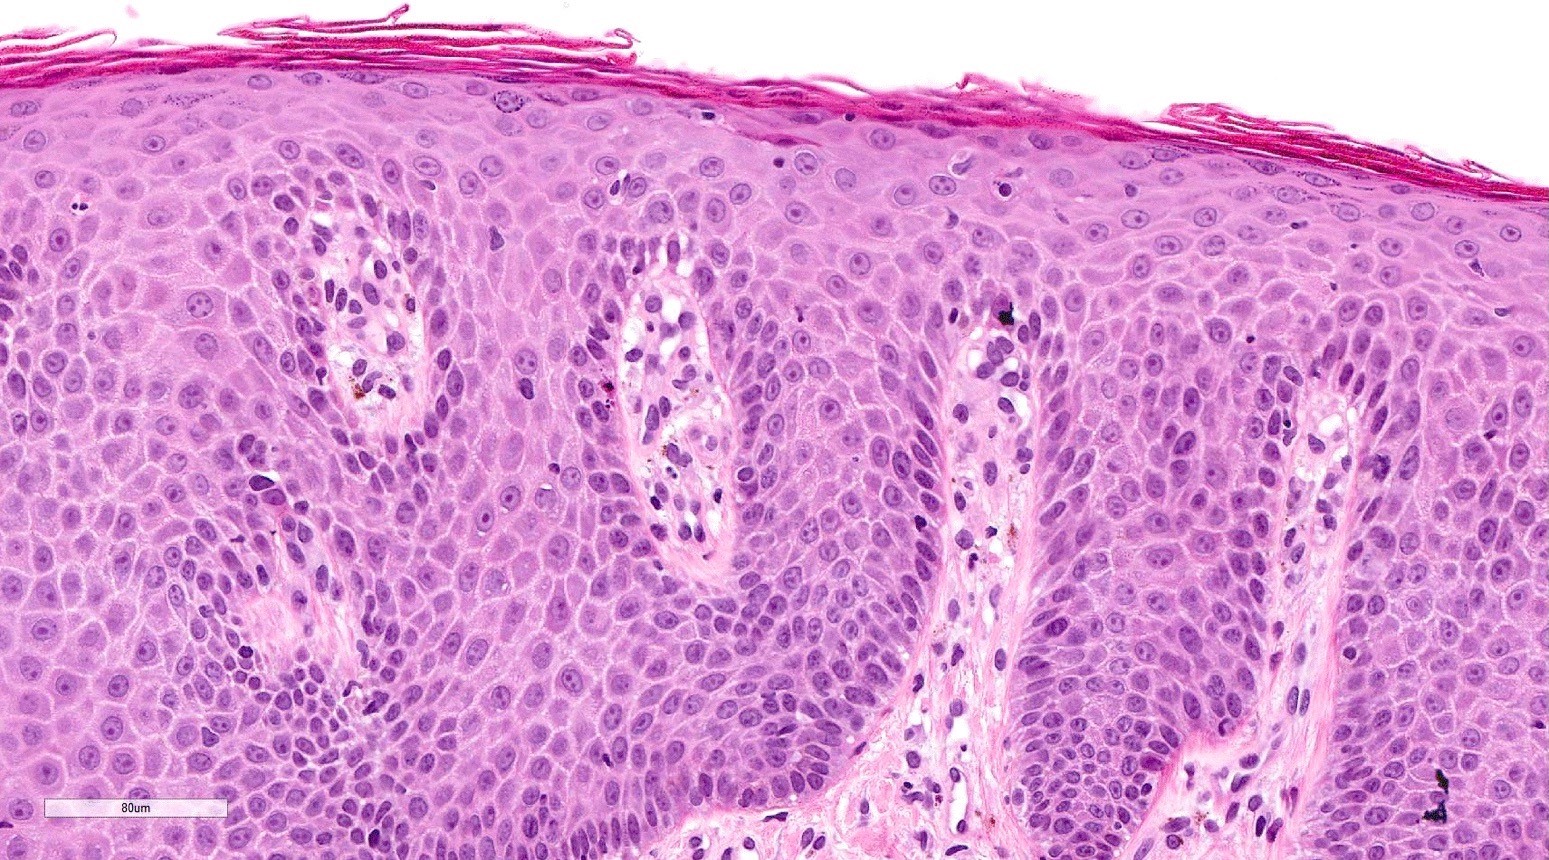

- Acute GVHD (Patterson: Weedon's Skin Pathology, 4th Edition, 2015)

- Mild to moderate superficial perivascular lymphocytic infiltrate with exocytosis of inflammatory cells into the epidermis and basal vacuolation, interface dermatitis

- Scattered, shrunken, eosinophilic keratinocytes with pyknotic nuclei, at all levels of the epidermis; often accompanied by 2 or more lymphocytes, producing the satellite cell necrosis - lymphocyte associated apoptosis

- Occasionally, rare eosinophils can be present; melanin incontinence is prominent in patients with darker skin types

- If severe, subepidermal microvesicles, subepidermal blisters and epidermal necrosis

- Rare variants: psoriasiform

- Psoriasiform epithelial hyperplasia

- Subtle vacuolar interface changes

- Satellite cell necrosis (Am J Dermatopathol 2018;40:511)

Microscopic (histologic) images

Contributed by Silvija P. Gottesman, M.D. and Ohoud Aljarbou, M.D.